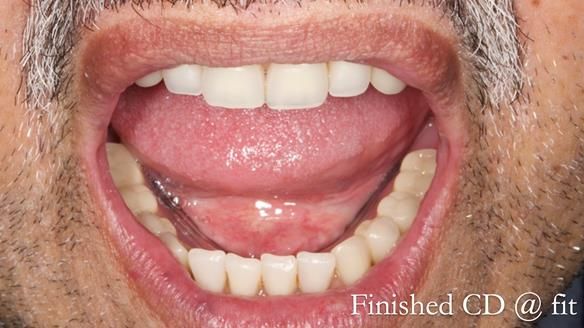

Rafique adapted superbly to the complete dentures not only because they fitted well. He had a positive approach to the treatment and put the effort in to work with the new dentures rather resisting them. I can’t stress how important this is for success with dentures.

Even if dentures are technically excellent their success hinges on the patient's willingness to cooperate. Without the patient's commitment to working with them, even the best made dentures may fall short.